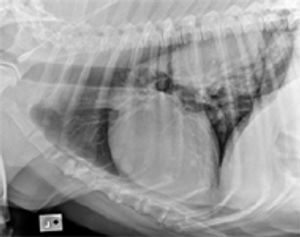

Thoracic radiographs should initially be evaluated for positioning, technique (exposure factors), and the presence of any artifacts that might affect interpretation.